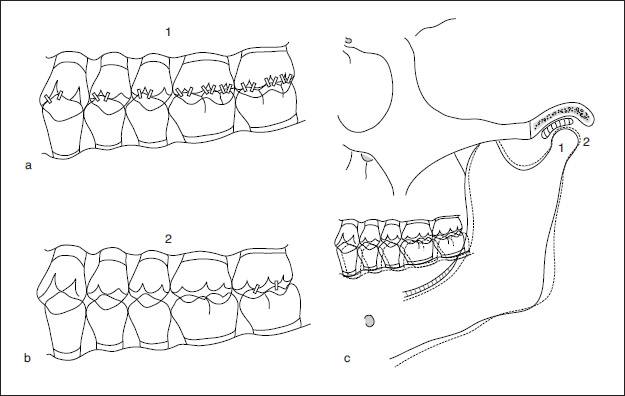

Terms related to clinical applications also must be considered. Undoubtedly the most defined term in prosthodontics is centric relation, closely followed by maximal intercuspal position and centric occlusion position. The basic definition of centric relation is the physiologic relationship of the mandible to the maxilla when both condyles are properly related to their articular discs and the condyle-disc assemblies are stabilized against the posterior slopes of the articular eminences. This relationship may occur at varying degrees of mandibular opening, but must precede the downward and forward movement (ie, translation) of the condyles. This definition may be embellished in many ways, but if the basic premise of a bone-to-bone relationship is maintained, acceptance of this simple concept can eliminate confusion. Maximal intercuspal position may be defined as the most complete interdigitation of the teeth independent of condylar position. Hence, maximum intercuspation is a maxillomandibular relationship determined by tooth-to-tooth relationships. Centric occlusion position represents the first contact of the teeth that occurs when the mandibular condyles are in centric relation. Therefore, centric occlusion position is a maxillomandibular relationship dictated by bone-to-bone relationships (Fig 1-8).

Fig 1-8 (a) Maximal intercuspal position is the most complete interdigitation of the teeth and is independent of condylar position. (b) Centric occlusion position is the first contact of the teeth that occurs when the mandibular condyles are in their centric relation positions. (c) Maximum intercuspation and centric relation can be coincident if the occlusion is appropriately developed or properly adjusted. This would occur with the teeth in position 1 and the temporomandibular joints in position 2.